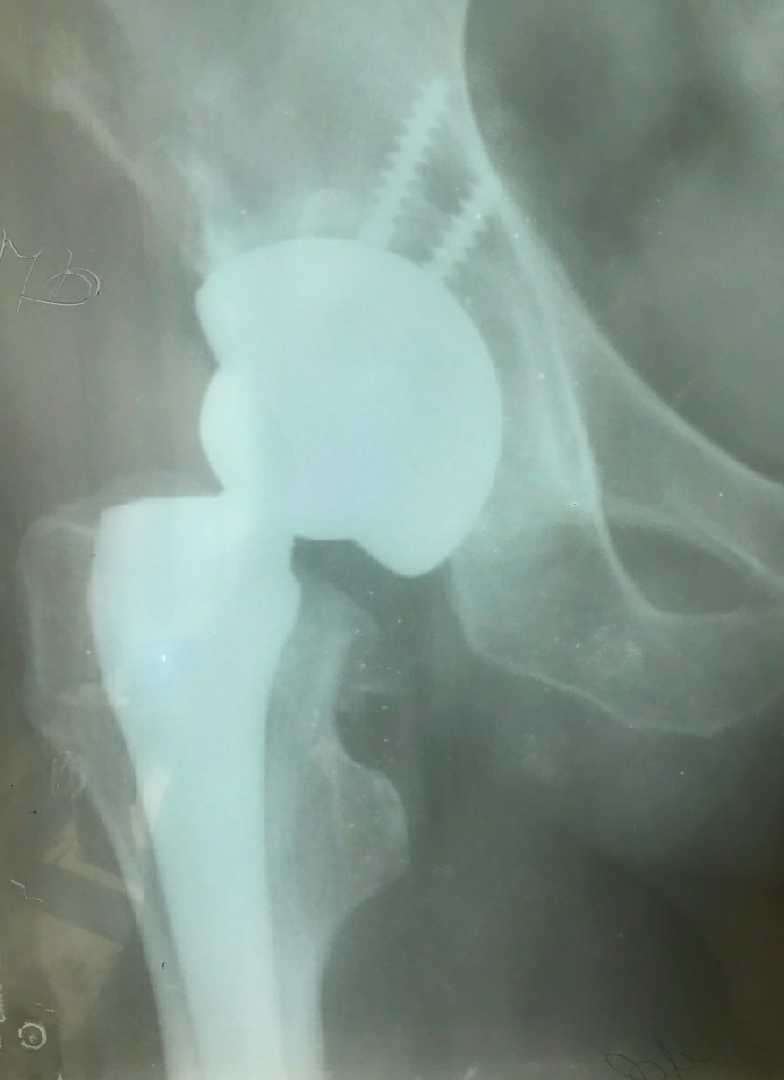

01 Бер 2024 Маршрут потрапляння пацієнта на хірургічне та/або реабілітаційне лікування _протезування_ у МЦ БО БФ -Суперлюди- Переглянути повністю...